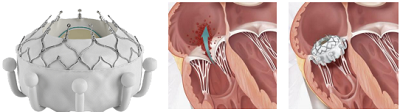

EVOQUE(愛德華)

EVOQUE 瓣膜是美國愛德華公司設(shè)計(jì)的一款自膨脹式三尖瓣瓣膜,由自膨式鎳鈦合金支架、牛心包瓣葉、編織物裙邊以及瓣葉夾持裝置組成。其固定方式主要依靠 9 個(gè)倒勾的瓣葉夾持件,輸送狀態(tài)時(shí)夾持件伸直,送入輸送鞘管后夾持件倒勾向心房,與自身瓣膜支架徑向支撐之間形成夾持力夾住瓣葉。操作時(shí)經(jīng)股靜脈途徑將瓣膜送至三尖瓣位置后同軸釋放。瓣膜釋放時(shí)先探出抓捕裝置以牢牢抓住瓣葉,經(jīng)位置調(diào)整后再緩慢釋放出瓣架。

TRISCEND 研究中接受治療的患者的一年臨床結(jié)果顯示出良好的安全性、有效性和患者生活質(zhì)量改善的結(jié)果[65]。后續(xù) TRISCEND Ⅱ研究將進(jìn)一步對(duì)比應(yīng)用 EVOQUE 瓣膜行 TTVR 與優(yōu)化藥物治療為重度三尖瓣反流患者所帶來的臨床獲益,該研究尚在進(jìn)行中(NCT04482062)。一項(xiàng) 25 例的人道救助治療數(shù)據(jù)顯示,術(shù)后 30 天隨訪中有 2 例患者出現(xiàn)傳導(dǎo)阻滯需要安裝起搏器[66]。另外,采用此類錨定方式的人工瓣膜均

▲ EVOQUE 瓣膜支架系統(tǒng)及植入示意 (資料來源:公司官網(wǎng),蛋殼研究院)